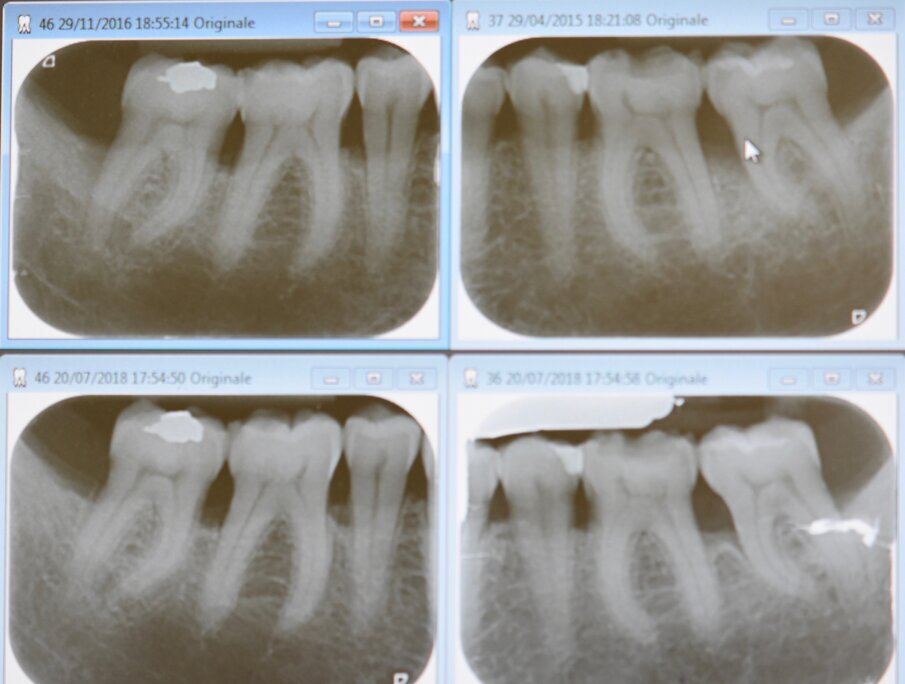

Fig. 1 - Miglioramento dei siti trattati con TPNC evidenziabile attraverso l’RBL (Radiographyc Bone Loss) in un paziente con parodontite di Stadio III e Grado A.